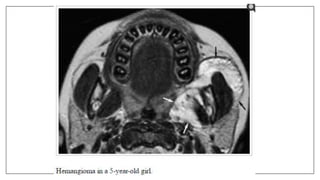

Pathologies